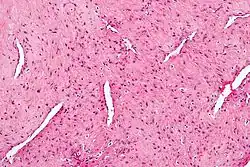

| Micrograph of a nasopharyngeal angiofibroma. H&E stain. | |

Grossly, it is a firm mass that may be yellow, dark red, or even black. Histologically, it presents with several vascular spaces of varying sizes and wall thicknesses as well as fibrous or collagenous stroma with fibroblasts. Mast cells are common. Mitotic figures are usually not present.[5]